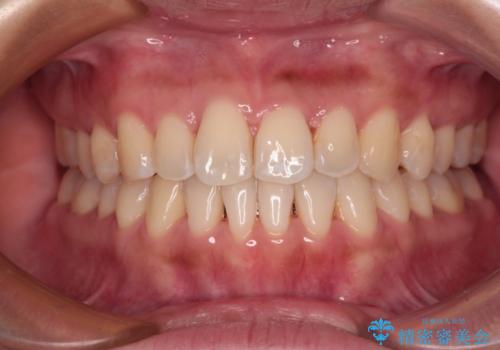

- 口元の突出感と口の閉じにくさを気にして来院された患者様です。

上下左右第一小臼歯4本を抜歯し、ワイヤー装置にて口元を引っ込めるよう矯正治療を行うこととしました。

2年~2年半が治療期間の目安でしたが、順調に治療が進み、1年9か月で満足のいく歯列となりました。